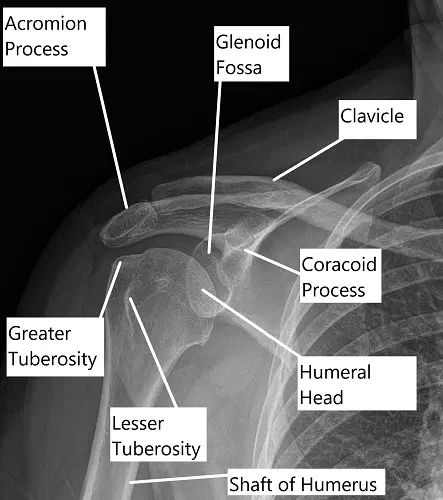

X-ray showing shoulder anatomy